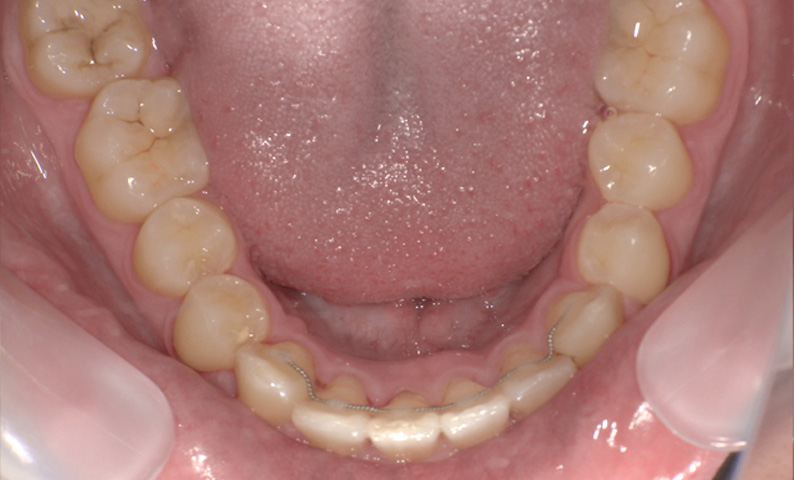

症例_009 「上下の前歯」症例

治療期間:7ヶ月金額:54万円+税20代女性捻転歯一部の反対咬合前歯のガタガタ